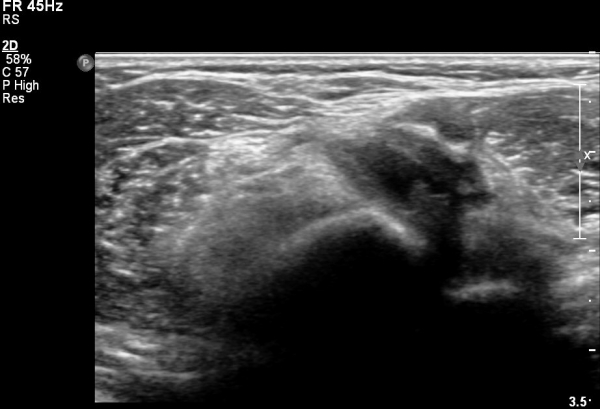

ÀÌµÎ¹Ú±Ù°Ç Á¾´Ü¸é°Ë»ç¿¡¼­ ¿ä°ñµ¹±âÀÇ µ¹Ãâ°ú °ñ±ØÀÌ °üÂûµÇ°í À̵θ·±Ù°ÇÀº Àú¿¡ÄÚ ºÎÁ¾°ú ¿¬°á ¼Ò½ÇÀÌ °üÂûµÊ(»çÁø 4, 5).

Àü¿ÏÀ» ȸ³»ÇÑ »óÅ¿¡¼­ ÆÈ²ÞÄ¡ µÚÂÊ¿¡¼­ ¿ä°ñµ¹±âÀÇ µ¹Ãâ°ú ÀÌµÎ¹Ú±Ù°Ç ºÎÂøºÎÀÇ Àú¿¡ÄÚ ºÎÁ¾ÀÌ °üÂûµÊ(»çÁø 6).